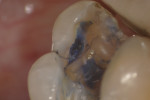

In this case, the patient had an asymptomatic maxillary left first molar with a conservative existing occlusal-lingual amalgam restoration that showed no signs of recurrent decay radiographically but, clinically, at high magnification demonstrated a gray shadow around the periphery of the amalgam, which is a sign of marginal leakage and recurrent decay. Several fractures were seen as well at higher magnifications on the occlusal surface. The tooth was photographed at low, medium, and high magnifications (Figure 3A; Figure 3B; Figure 3C) and then the rubber dam was placed. Initial application of methylene blue dye to the enamel cracks demonstrated substantial cracks on the occlusal surface and a pair of cracks on the mesial marginal ridge, one of which was large enough to house debris (Figure 4A; Figure 4B; Figure 4C). There was a substantial crack on the midbuccal of the tooth in an anatomic groove which, according to Clark, is a low-risk area for large fractures. Additional fractures ran across the transverse ridge connecting the mesial and distal pits and, in addition, ran up the mesial-lingual cusp from the mesial pit.

The amalgam restoration was removed and the tooth was again stained with methylene blue dye to show a dramatic and large vertical crack that runs from the mesial interproximal area to the mid-buccal groove (Figure 5A; Figure 5B; Figure 5C). Given the location, type, and degree of the fracture, combined with dentinal fractures in the rest of the tooth, a resin core build-up was completed, and the occlusion adjusted (Figure 6A; Figure 6B; Figure 6C). The patient was shown the photographs, which were sent away for insurance preauthorization for a full-coverage restoration, and the patient was advised of the definitive treatment plan for this tooth, which includes the possibility that endodontic therapy may be required should the tooth become symptomatic with signs of irreversible pulpitis. The existing buildup restoration provides an opportunity to evaluate pulpal response prior to the definitive restoration being placed, after the insurance predetermination of benefits is returned to the dental office for this patient.